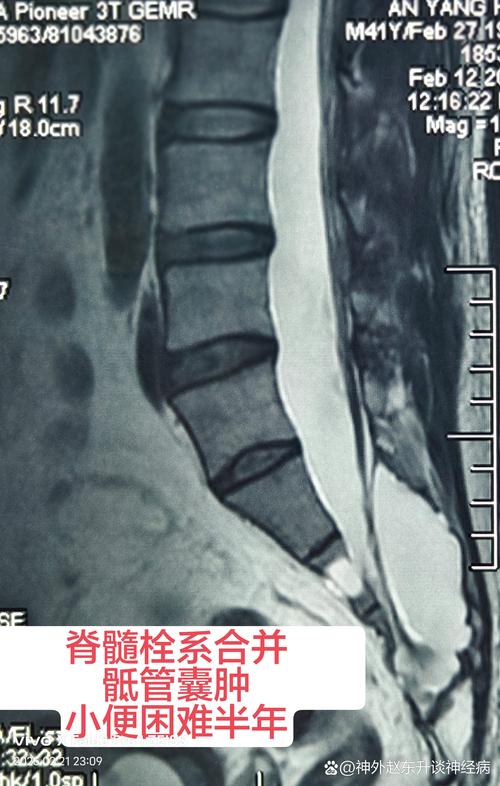

- 明确诊断是前提:在进行任何中医治疗前,必须通过腰椎MRI等检查,明确诊断骶管囊肿的大小、位置,并与医生充分沟通,排除其他严重疾病。